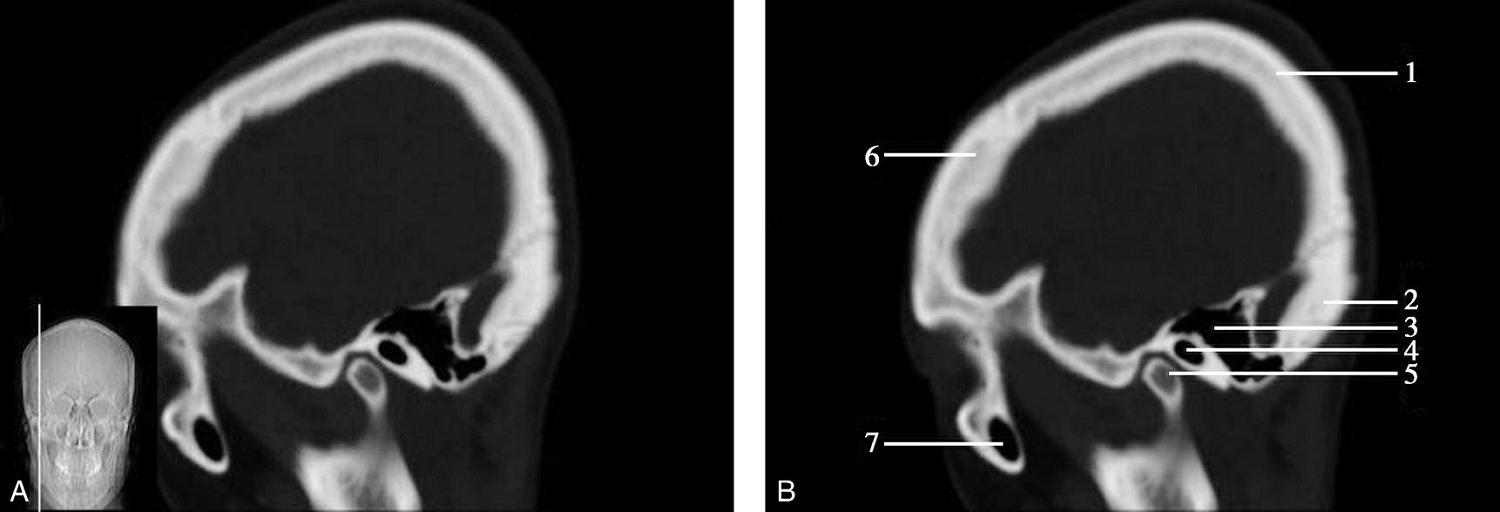

重要结构:卵圆孔、棘孔、破裂孔、斜坡、颞骨岩部、颈静脉孔(图1-2-1、图1-2-2)。

图1-2-1 颅底层面

A.横断面;B.横断面标注

1.晶状体;2.筛窦;3.颞肌;4.中颅窝底;5.外耳道;6.延髓;7.乙状窦;8.小脑半球;9.眼球;10.眼眶;11.上颌窦;12.蝶窦;13.乳突;14.耳郭;15.小脑蚓部;16.枕内隆凸

图1-2-2 颅底层面(骨窗)

1.鼻骨;2.筛窦纸板;3.颧骨眶突;4.翼腭窝;5.蝶骨大翼;6.卵圆孔;7.破裂孔;8.颞骨颧突;9.棘孔;10.斜坡;11.颞骨岩部;12.乳突;13.颈静脉孔;14.枕乳突缝;15.枕骨;16.枕内隆凸

层面前部呈开口向前的“V”字形,正中为鼻中隔,向两侧依次为筛窦和眼眶,眼眶内前部为眼球,后部为眶脂体。翼腭窝位于眼眶后部,窝内含有脂肪并有上颌神经通过。层面中部为蝶骨体,蝶骨体中部可见含气蝶窦,蝶窦后方为枕骨基底部,两者呈前后关系,其上面构成斜坡。蝶窦两侧为蝶骨大翼,其后外侧缘处由前向后可见卵圆孔和棘孔,分别有下颌神经和脑膜中动脉通过。斜坡外侧、岩骨尖前方为破裂孔。蝶骨大翼与眶外侧壁的颧骨借颧弓相连,颧弓和蝶骨大翼之间有咬肌及颞肌。层面中部外侧为外耳道。颞骨岩部呈“八”字形,相互之间借破裂孔软骨、蝶岩软骨结合和岩枕软骨结合连接。岩部后外侧的乳突部内可见乳突小房,乳突部与枕骨相接。岩骨后部可见颈静脉孔,内有颈内静脉、舌咽神经、迷走神经和副神经通过。层面后部为颅后窝,其内可见延髓,延髓前方为延髓前池,内有椎动脉,后外侧为小脑半球下部,后方为第四脑室、小脑扁桃体及小脑蚓部。

破裂孔、卵圆孔、棘孔及斜坡等均为重要的解剖结构,临床常见疾病如鼻咽癌常侵犯上述结构(图1-2-3)。颈静脉孔区较常见的肿瘤为颈静脉球瘤,常伴有颈静脉孔及其邻近骨质的破坏(图1-2-4)。